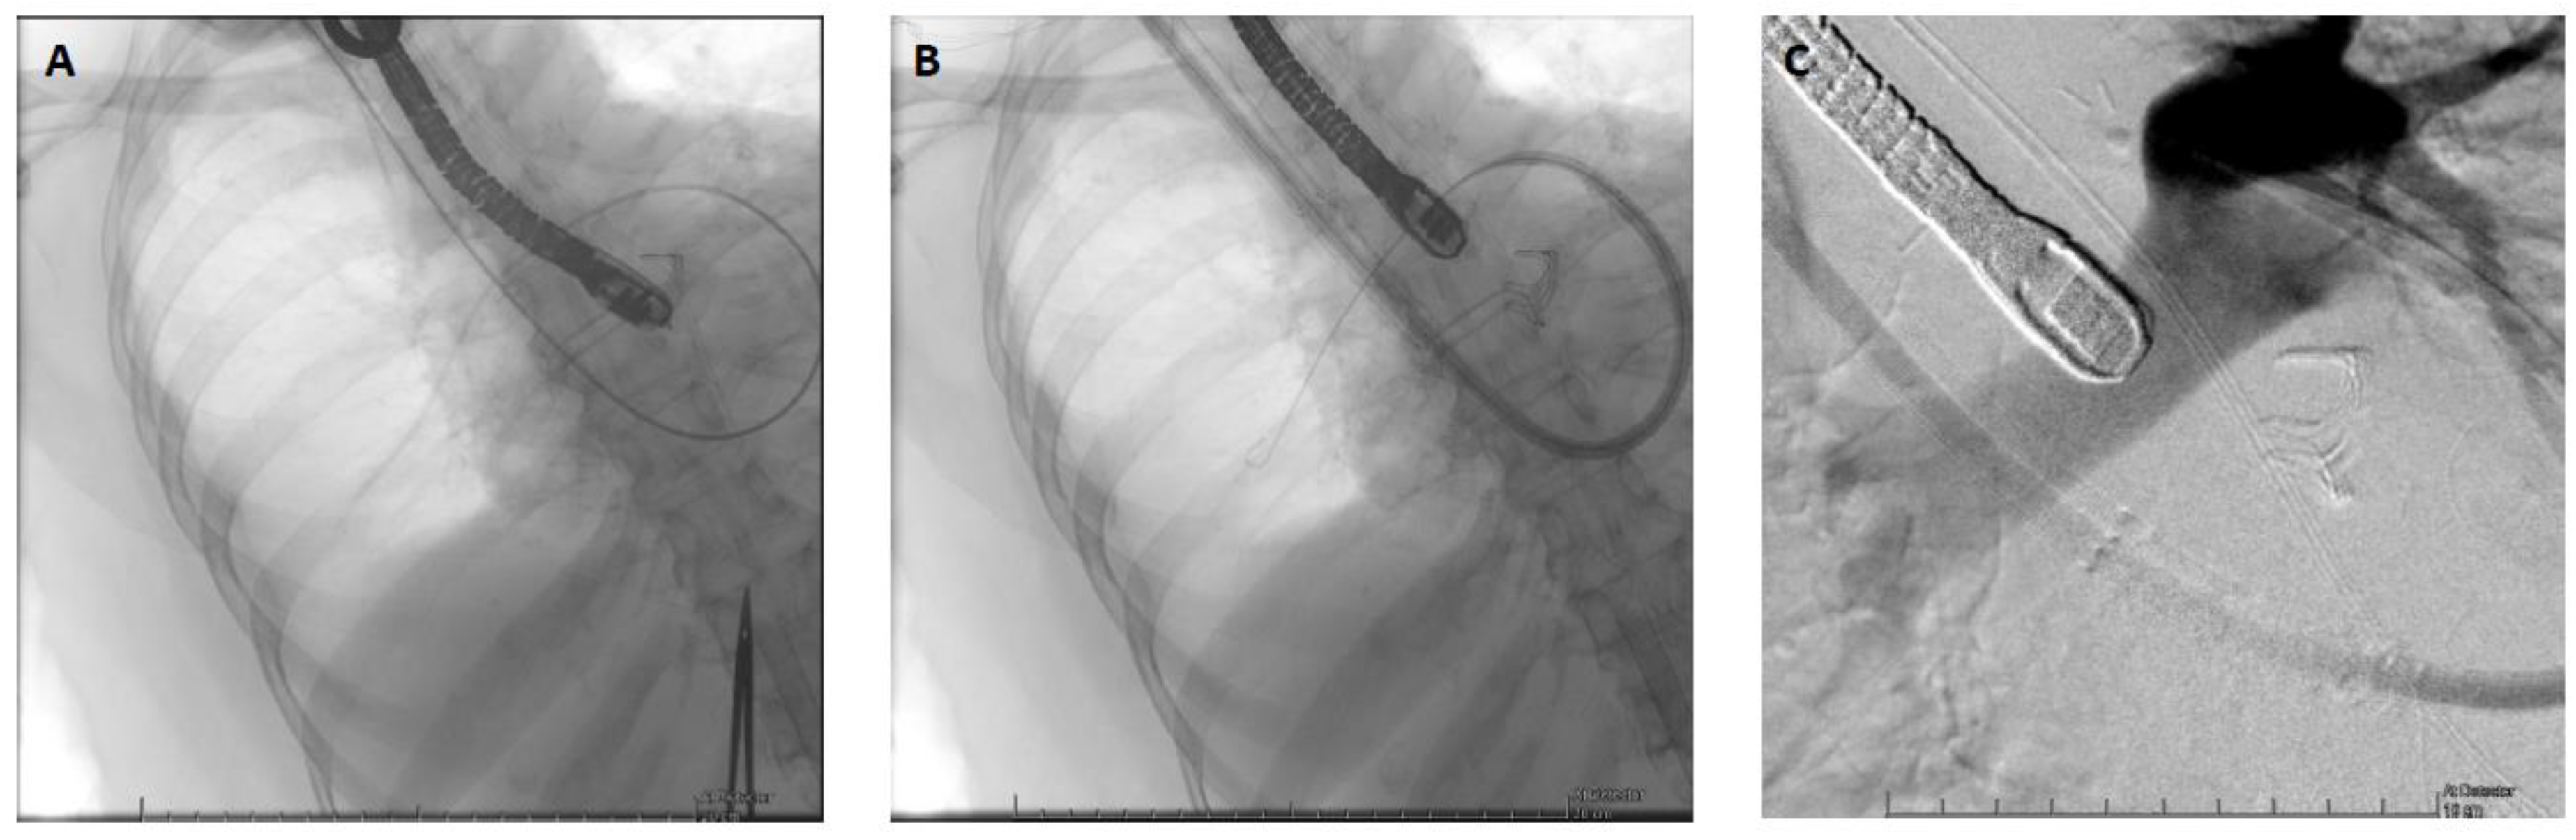

When the patient stabilized and organ function was restored, sedation was stopped, allowing neurological evaluation. Awakening occurred on postoperative Day 4, without any neurological sequelae, and the patient was extubated. Levosimendan was initiated on Day 10, and fluid depletion was achieved through diuretic administration. Nonetheless, the patient could not be weaned off VA-ECMO due to an akinetic and nonrecruitable right ventricle, despite inotropic support. It was decided to wait further on MCS. The patient was conscious, calm, and cooperative but remained bedridden because of the femoro-femoral VA-ECMO. After two weeks, the patient still could not be weaned off VA-ECMO. Indeed, below two liters per minute of blood flow, the patient showed both macrocirculatory and microcirculatory signs of ARF. The mean arterial pressure dropped, the central venous pressure (CVP) increased up to 25 mmHg, the SvO2 dropped from 60 to 30%, the lactate level increased up to 4 mmol/l, and the patient became oliguric. The TOE exam showed a severely dilated and akinetic RV (TAPSE = 4mm, S’ VD 2.3 cm/s, FAC RV = 10%), a small LV size with a preserved function and a LVOT VTI 10 cm/s. Due to her age and an INTERMACS 1 profile, the patient was not eligible, in our country, for a heart transplant or a definitive RVAD implantation (Heartmate III, modified insertion for the right ventricle). Faced with the prospect of prolonged weaning and no other therapeutic alternatives, VA-ECMO was switched to a temporary percutaneous RVAD by implanting a ProtekDuo cannula through the right internal jugular route (Figure 2). A CentriMagTM centrifugal pump (Abbott, Chicago, USA) without an oxygenator was connected to the cannula with an initial flow rate of 4 liters per minute. After a few minutes, the VA-ECMO components could be removed without any vasopressor support. After the initiation of the RVAD, intraoperative TEE showed a reconfiguration of the ventricles. The right ventricle was suitable unloaded by the RVAD, while the left ventricle resumed a circular shape with complete regression of the D-shaped sign (Figure 3). The hemodynamic tolerance of the RVAD was very good (lactate levels < 2 mmol/L, SvO2 > 60%, normal renal and hepatic function). The day after the implantation, the patient was out of bed, placed in a chair, and began rehabilitation. Slow and gradual weaning was instituted. In fact, during the following three weeks, a gradual reduction in the flow rate of the RVAD was carried out at a rate of approximately one liter per week. Interestingly, the serial TTE exam did not show a significant improvement in RV contractile function, but as the pulmonary pressure, pulmonary resistance and LVEDP remained low, the patient’s hemodynamics adapted and showed physiological similarities with a Fontan circulation. During gradual weaning, the renal and hepatic function was monitored daily (creatinine, BUN, AST, ALT, Bilirubine and Factor V levels) and we did not observe any biological signs of congestion or organ dysfunction. Finally, the patient could undergo explantation after 3 weeks of RVAD support. Closed monitoring for 5 additional days was carried out in the ICU. Right ventricular systolic function remained poor (three-dimensional RV ejection fraction (RVEF) = 26%, RV fractional area change (FAC) = 21%, severely reduced longitudinal function with global akinesia except for the apical segments of the anterior and lateral wall) but was well tolerated. CVP remained below 15 mmHg, SvO2 was above 60% with normal lactate levels, and renal and hepatic functions remained stable. Anticoagulation therapy was empirically initiated to prevent thromboembolic events, as the patient would likely not survive any abrupt increase in RV afterload. Diuretics and antihypertensive treatments were continued to maintain a low LVEDP. To be noted, during mechanical circulatory support, the patient did develop only minor ECMO-related complications. Minor bleeding at the canula site were noted after canulation and stopped rapidly after optimization of the coagulation profile. Femoral venous thrombosis (at the site of the cannula) was diagnosed after explantation and treated accordingly. We did not observe any Protekduo-related complications.

Figure 2. Insertion of the ProtekDuo cannula under fluoroscopy and TOE. A: Pulmonary artery catheter already positioned in the right pulmonary artery. B: Insertion of the ProtekDuo cannula on the guidewire. C: Confirmation of positioning by injection of contrast via the distal port of the ProtekDuo cannula with its tip located in the main trunk of the pulmonary artery. TOE: Transesophageal echocardiography.